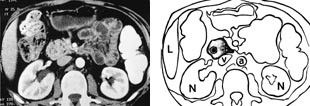

Pasient 1. En 19 år gammel kvinne hadde hatt magesmerter i noen år. Smertene ble kraftig forverret i forbindelse med diaré som oppstod etter en Syden-tur. Det tilkom amylasestigning til knapt 1 000 U/l, og peroralt inntak av annet enn vann provoserte frem magesmerter og brekninger. Røntgenundersøkelse av ventrikkel og duodenum viste en 2 – 3 cm lang stenose i nedadstigende del av duodenum (fig 2). Motiliteten i ventrikkelen var nedsatt, og det forelå retensjon i ventrikkel og øvre del av jejunum. Stenosen ble bekreftet ved gastroskopisk undersøkelse. CT av øvre del av abdomen med vann som peroralt kontrastmiddel (fig 3) viste en kort stenose i midtre nedadstigende duodenalavsnitt, hvor duodenum var omsluttet av smålobulært pancreasparenkym. Pancreas for øvrig var upåfallende. Magesekken var distendert etter vanninntaket, og distensjonen omfattet også duodenum proksimalt og distalt for stenosen. Pasienten responderte på total parenteral ernæring. Amylasen normaliserte seg. Ved utskrivning kunne pasienten spise normalt. Det ble antatt at pankreatitt i den annulære pancreas forbigående hadde gitt en høy gastrointestinal obstruksjon.

Slimhinnen er vanligvis normal. Pylorusinkompetanse og reversert peristaltikk kan forekomme (2, 7). Nyere radiologiske metoder kan diagnostisere den annulære pancreas. Ved CT kan selve annulus fremstilles i form av normalt pancreasvev som helt eller delvis omslutter andre del av duodenum (fig 3). Lavattenuerende peroralt kontrastmiddel (vann) og jodholdig kontrastmiddel intravenøst, som ble brukt hos aktuelle pasient (fig 3), er best for å fremheve kontrasten mellom duodenallumen og kontrastoppladende pancreasvev (2). Jod- eller bariumholdig kontrastmiddel i duodenum vil imidlertid kunne benyttes for å påvise selve det stenotiske tarmsegment inne i det tilsynelatende forstørrede pancreashodet (7). Hos aktuelle pasient var den del av duodenum som lå omsluttet av pancreashodet, ikke distendert av vannet. Anomalien kunne likevel diagnostiseres, da man i CT-snittene umiddelbart ovenfor og nedenfor pancreasringen så en dilatert duodenum som gradvis fikk et mer medialt forløp enn normalt og som smalnet av for å passere gjennom høyre del av pancreashodet. Like kaudalt for pancreashodet utvidet duodenum seg igjen. Vanligvis er stenosen minst 2 cm lang, og CT er derfor velegnet for å stille diagnosen, da det ved undersøkelse av pancreas benyttes kontinuerlige, maksimalt 5 mm tykke snitt. CT bør være førstevalg som metode pga. liten invasivitet og høy tilgjengelighet. Vanlig ultrasonografi vil også kunne gi mistanke om lidelsen ved funn av utspilt, væskefylt prestenotisk duodenum.